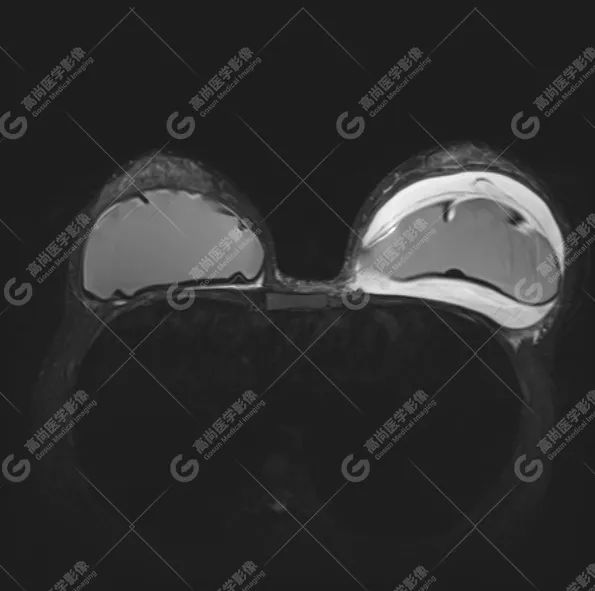

病例 5:乳腺假体植入术后 5 年余

双侧假体外包膜破裂(完全破裂),包膜周围可见内容物渗漏,伴内容物变性、包膜周围炎性反应。